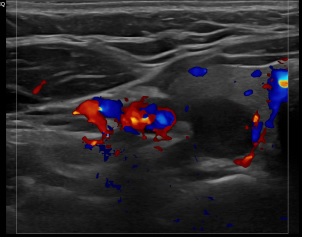

상기환자 외부건강검진이상소견으로 세침검사위해 내원하신 30대초반 여성분으로

의심스러운 갑상선 우엽 결절 세포검사 진행후 갑상선암으로 진단되었습니다